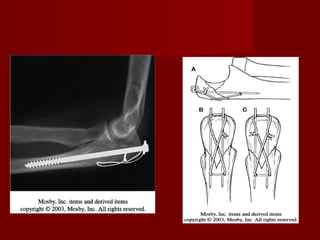

FRACTURAS DEL

OLECRANON.

   En fracturas       no desplazadas,     debe

realizarse reducción cerrada.

   La reducción debe ser exacta.

   Las complicaciones más frecuentes son:

seudoartrosis y la pérdida de la movilidad,

sobre todo en extensión.

   Su mecanismo puede ser: directo e indirecto.

  Los métodos habituales del tratamiento

quirúrgico pueden ser:

1. Reducción abierta y fijación interna con cerclaje

funcional en ocho de guarismo.

2. Fijación medular.

3. Combinación de fijación medular con aguja o

tornillo y cerclaje a tensión.

4. Placa moldeada a mano y tornillos.

5. Extirpación del fragmento proximal.

 Ventajas de reducción abierta y fijación

interna:

1. Permite la reducción anatómica.

2. Permite movilización precoz.

3. Conserva la estabilidad del codo.

4. Se mantiene poder extensor del triceps

Extirpacion de fragmento.

 Se    puede        extirpar

hasta el 80%.

 Indicaciones:

1.   Fracturas conminutas

graves.

2.   Fracturas

extraarticulares.

3.   Fracaso        de     la

reducción.

4.   Pseudoartrosis.

5.   Tratamiento retrasado.

6.   Fracturas abiertas tipo